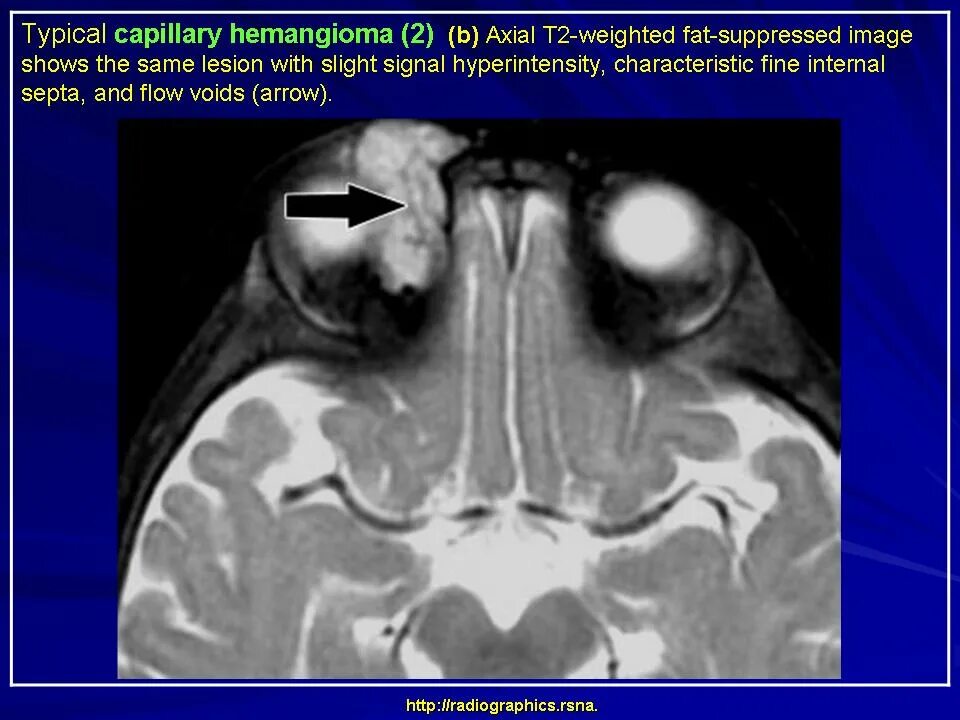

Данные кт